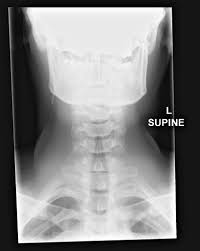

Shunt obstructions may be confirmed with radioisotope examination or with fluoroscopically guided injection of iodinated contrast material into the shunt reservoir. Ap and lateral radiographs of the skull shows migration of the vp shunt catheter tip out of its right sided burr hole in the skull. Most pediatric patients with hydrocephalus are treated with ventriculoperitoneal vp shunt placement.